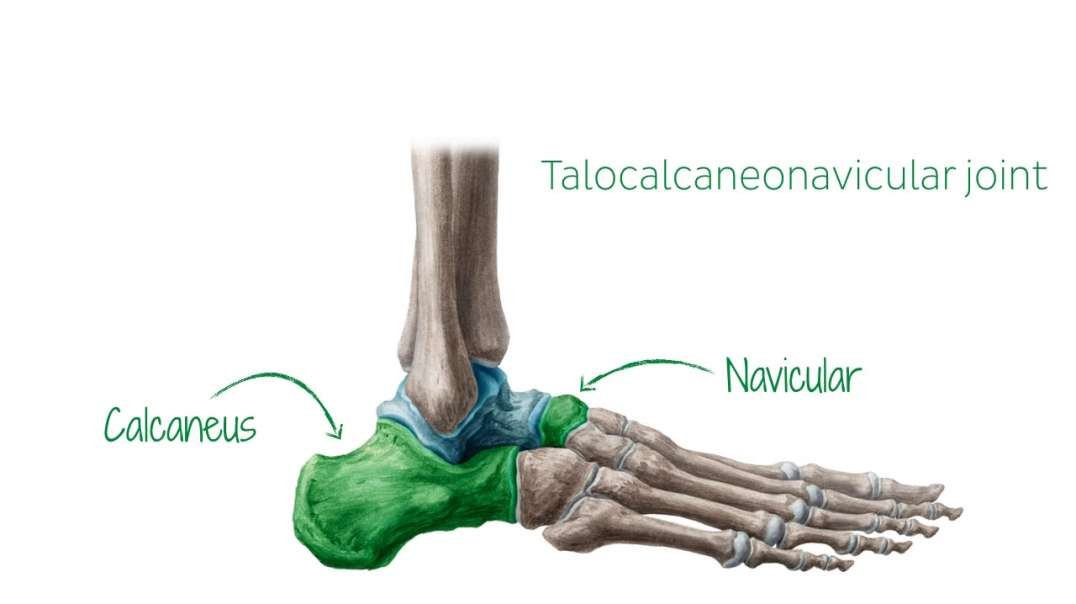

Joints and blood supply of talus

Joints and blood supply of talus kenhub